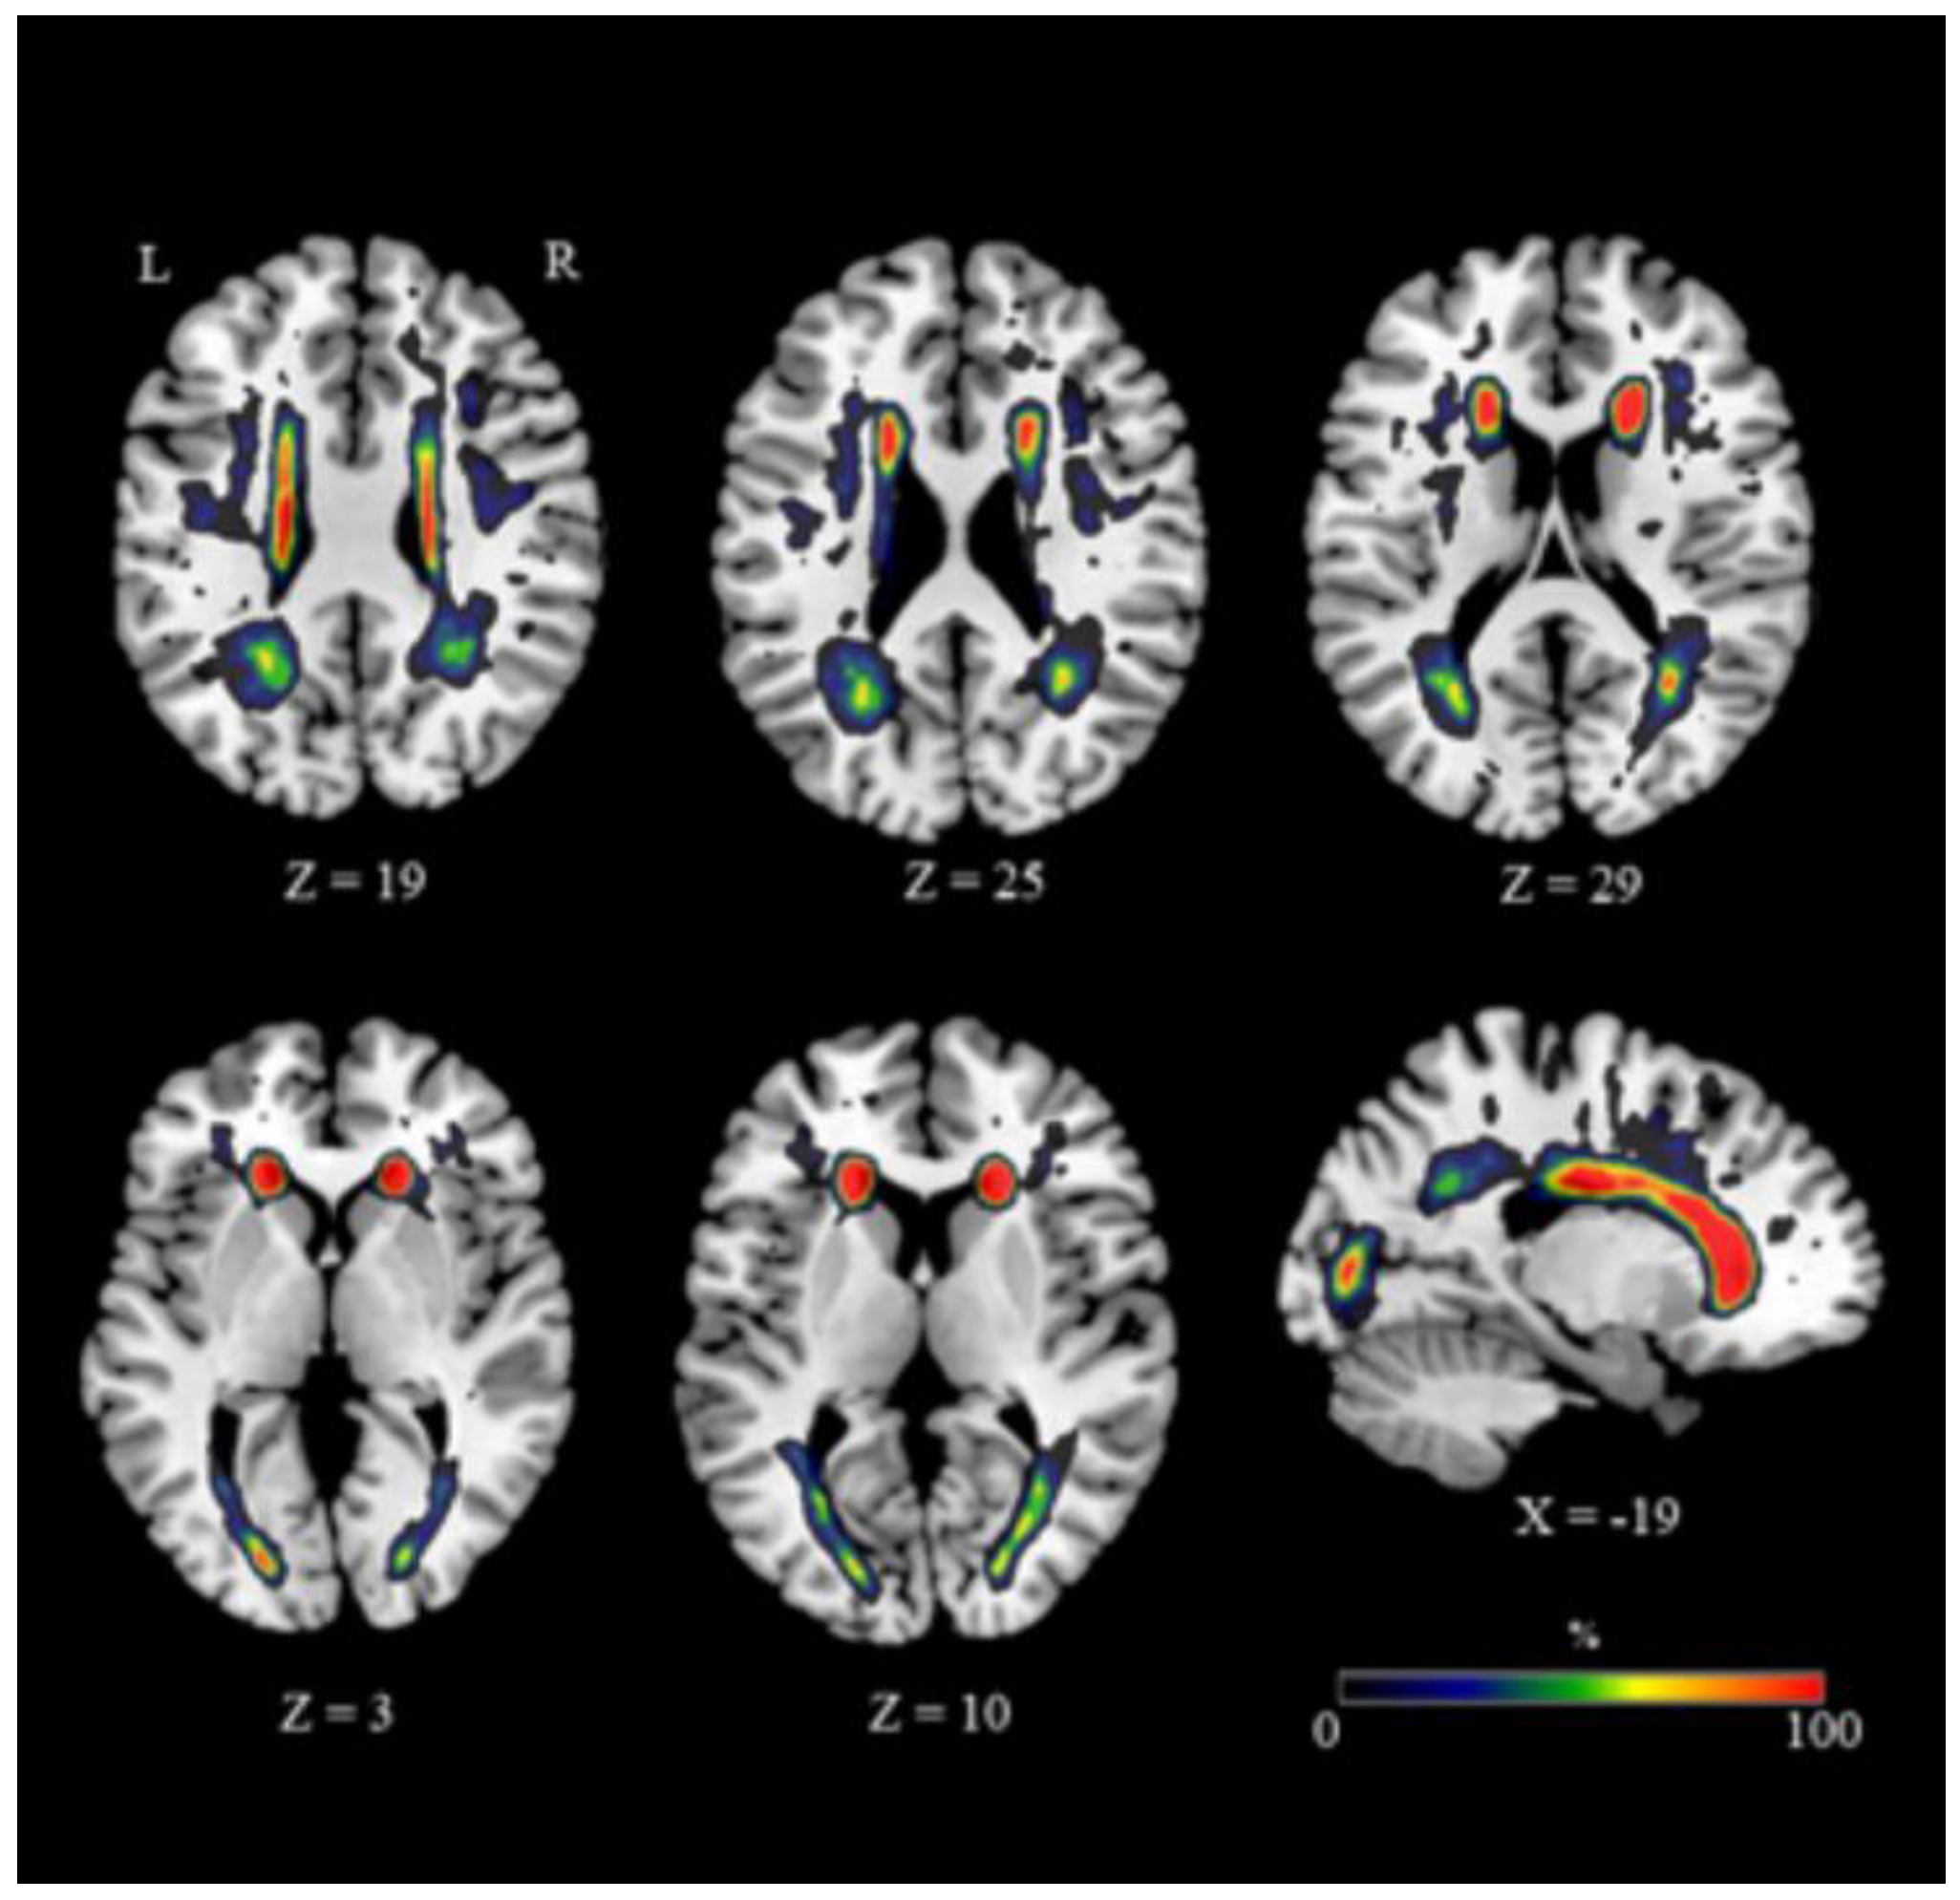

3.2. Regional Distribution and Volume Measurement of White Matter Hyperintensities (WMH)

3.3. Hippocampus–ROI Analyses